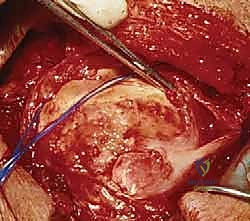

يُجري الجراح شقاً جراحياً دقيقاً (حوالي 5 إلى 7 سم) فوق مفصل الكتف. يتم فصل ألياف العضلة الدالية (Deltoid) بعناية فائقة للوصول إلى الكفة المدورة دون إتلاف العضلات السطحية.

المرحلة الثانية: تجميل الأخرم (Acromioplasty) وإزالة الضغط

قبل إصلاح الوتر، يجب معالجة سبب التمزق. يقوم الدكتور هطيف بإزالة الجراب الملتهب (Bursa) الذي يسبب الألم. ثم يستخدم أدوات دقيقة لإزالة النتوءات العظمية من أسفل عظمة الأخرم، مما يوسع المساحة ويمنع احتكاك الوتر المُصلح لاحقاً.

في حالات التمزقات الضخمة، قد تكون الأوتار متراجعة وملاصقة للعظم ومغطاة بالتليفات. هنا تبرز أهمية الجراحة المفتوحة، حيث يتم تحرير الأوتار بعناية فائقة وإعادتها إلى مرونتها الطبيعية لتصل إلى مكان تثبيتها الأصلي دون شد مفرط.

المرحلة الثالثة: زراعة الخطاطيف وخياطة الأوتار

يتم تحضير "بصمة الوتر" (Footprint) على رأس عظم العضد عن طريق تقشير العظم بلطف لتعزيز النزيف الخفيف الذي يجلب الخلايا الجذعية وعوامل النمو لتسريع التئام الوتر بالعظم.

ثم يتم زرع خطاطيف جراحية (Suture Anchors) متطورة (مصنوعة من التيتانيوم أو مواد قابلة للامتصاص) داخل العظم.

هذه الخطاطيف متصلة بخيوط جراحية فائقة القوة. يقوم الدكتور هطيف بتمرير هذه الخيوط عبر الوتر الممزق باستخدام تقنيات خياطة معقدة (مثل صف مزدوج Double Row) لضمان توزيع الضغط وتوفير تثبيت ميكانيكي صلب.

يتم ربط العقد الجراحية بإحكام، ويتم اختبار حركة الكتف على طاولة العمليات للتأكد من متانة الإصلاح وقدرة الوتر على تحمل الشد.